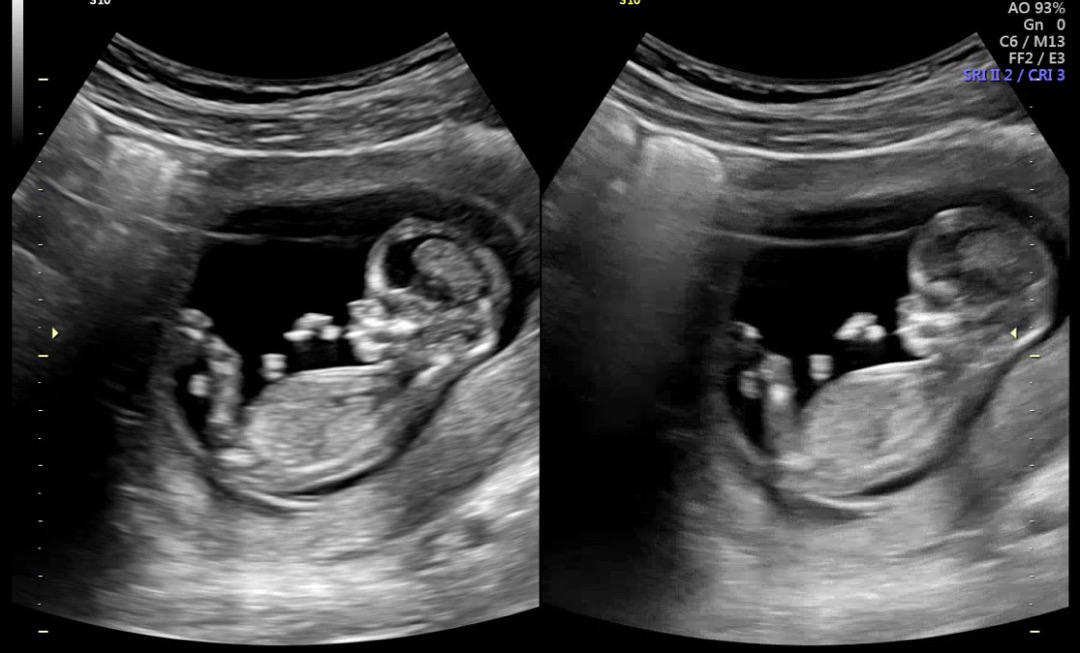

3주만에 3키로 빠져서 걱정했는데 아가는 잘크고있네용 입덧 없는데 얼마나 더먹어야될까요……??기형아 1차 목투명대 1.0cm 정상 받구 갑상선 수치 높게나와서 재검하고 왔어여,,,,성별 슬쩍 물어봤는데 다음진료때 알려쥬신다구 안알려주셧어영ㅠㅠㅠ12주 5일차인데 이걸 보고 성별을 알수있나요??초음파 영상으로 아무리 봐도 모르겠네요 다리사이 초음파영상은 없는데 그냥 다음진료까지 기다려야될까봐요,,,ㅠㅠ